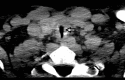

BACKGROUND The role of tracheostomy during the coronavirus disease 2019 (COVID-19) pandemic is still to be determined, and the complication rate of the tracheostomy in COVID-19 patients is still unknown. Postintubation tracheal stenosis is a well-known risk of prolonged endotracheal intubation, but it is too early to define the existence of any difference among the COVID-19 cohort of patients and non-COVID-19 patients. This report is of 2 cases of COVID-19 pneumonia that required tracheostomy and prolonged endotracheal intubation, which were followed by delayed tracheal stenosis. CASE REPORT Case 1. A 54-year-old male was admitted to our hospital (Biella, Italy) for severe acute respiratory syndrome coronavirus-2 (SARS-CoV-2) infection. The patient underwent orotracheal intubation, progressively improving his breathing function, and was discharged after 20 days. Ten days later, the patient presented with severe respiratory distress. Computed tomography (CT) scan and bronchoscopy showed signs of tracheal stenosis. We administered intravenous steroids for 10 days. The patient showed increasing improvement in his breathing function and was discharged with no other signs of respiratory distress. Case 2. A 43-year-old male was admitted to our hospital for SARS-CoV-2 infection. The patient underwent orotracheal intubation, progressively improving his breathing function, and was discharged after 25 days. Eighteen days later, the patient came to our emergency room with severe respiratory distress. CT scan and bronchoscopy showed signs of tracheal stenosis. The patient had to undergo tracheal resection. CONCLUSIONS The 2 cases presented in this report have shown that even when patients recover from severe COVID-19 pneumonia requiring tracheostomy and mechanical ventilation, tracheal stenosis should be recognized as a potential complication and careful follow-up is required.